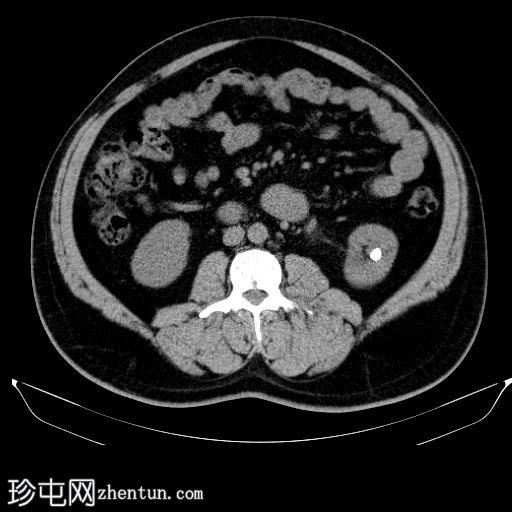

轴位

平扫

左肾盂及肾盏系统内可见多发边界清晰的高密度结石,最大直径约2 cm,平均CT值约418 HU。

结石呈典型的球形形态。

左肾盏系统及肾盂轻度扩张至肾盂输尿管连接处,提示肾盂输尿管连接处梗阻,但未见输尿管扩张或肾周脂肪浸润。